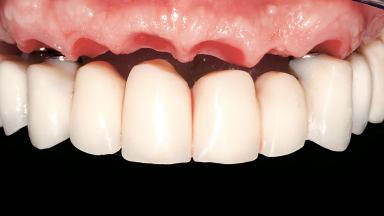

Immediate Loading of Six Implants in the Maxilla and Final Restoration with a Full-Arch CAD/CAM Zirconia FDP

A 63-year-old male patient was referred for a consultation and treatment of partial edentulism in the maxilla. The patient presented with residual anterior teeth and declined a partial removable prosthesis. He reported that the maxillary posterior teeth had been extracted due to mobility and periodontal disease two months before the consultation. The patient’s chief complaint was that his residual maxillary teeth were mobile and that he was unable to chew. The patient’s desire was a stable and comfortable fixed maxillary rehabilitation. The patient was a light smoker (fewer than 10 cigarettes/ day), and his medical history was without significant findings. He was not on any regular medication at the time of consultation. The extraoral examination revealed a normal physiognomy with a correct distribution of the facial thirds. The patient presented a low lip line, and the transition line between teeth and soft tissues was not exposed during a forced smile.

Abutment Type CAD/CAM

Prosthesis Type FDP

Defining Characteristics Fully edentulous upper jaw to be rehabilitated with an implant-borne fixed dental prosthesis